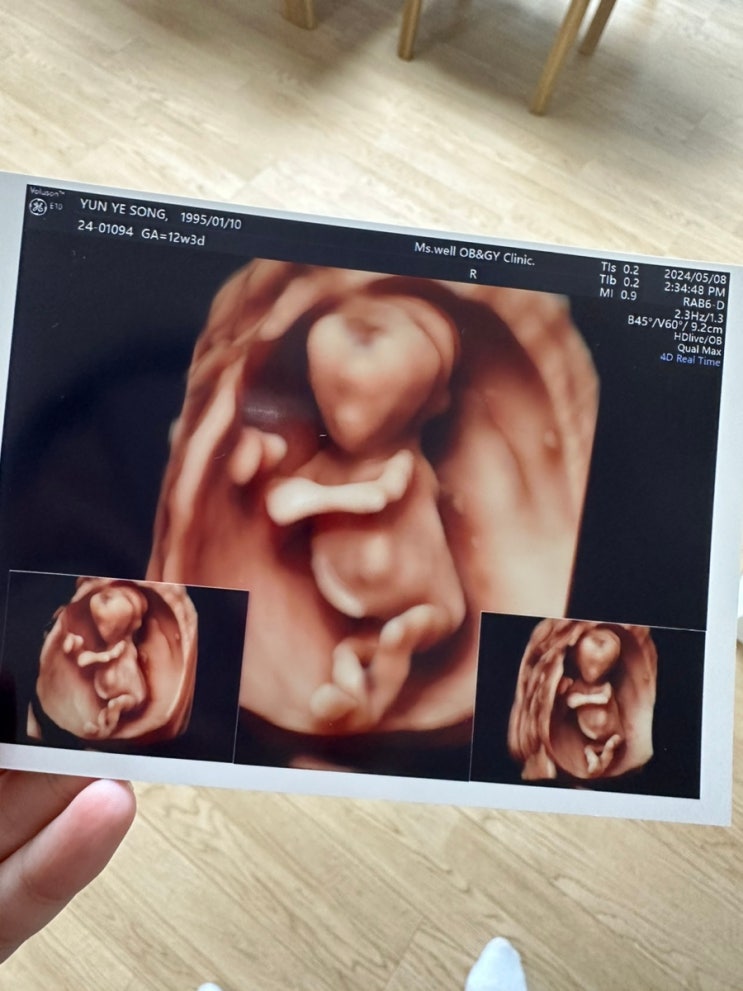

[임신 12, 13주차] 실바니안패밀리 극장판 / 12주 정밀초음파 / 1차 기형아검사 / 근호 집들이

오늘은 어린이날~~~~ 어린이는 아니지만 내가 좋아하는 실바니안 패밀리 극장판을 한다길래 센텀까지 넘어...